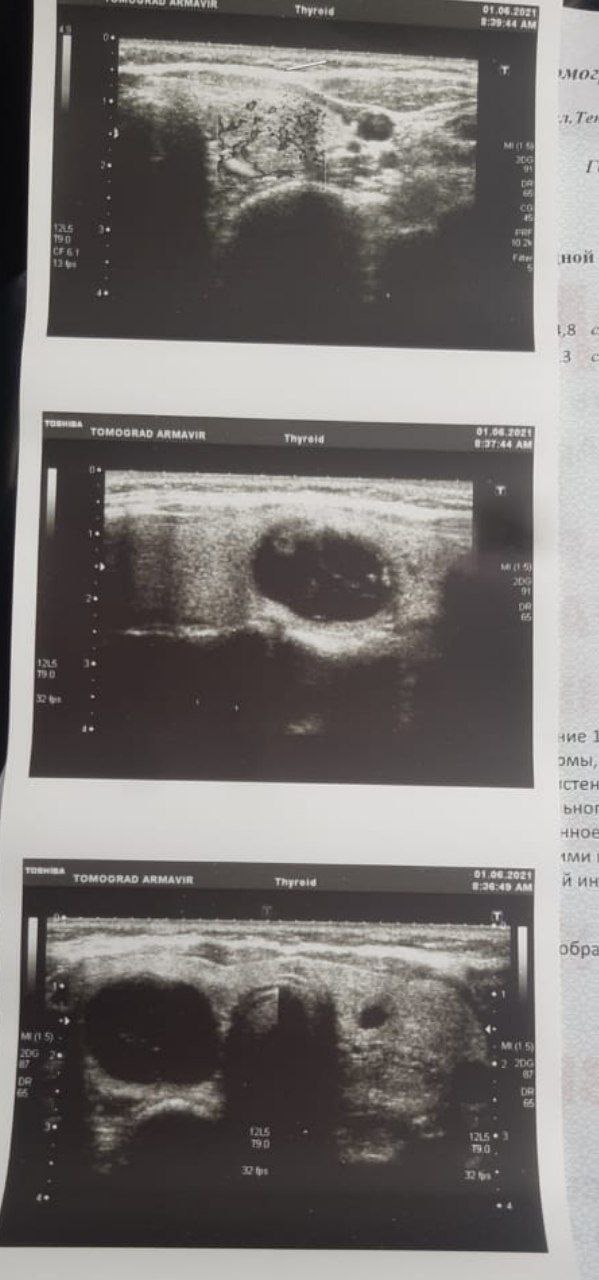

#вопрос.  Попросила написать девушка, 28 лет, 2 родов, курение. Недавно заметила у себя на шее с одной стороны уплотнение. Направилась на УЗИ щитовидной железы. Вот результат, просим врачей дать рекомендацию, по дальнейшим действиям. Спасибо заранее.